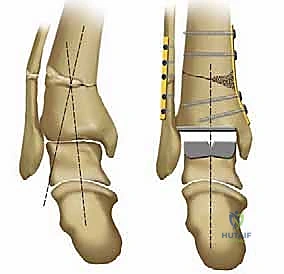

* التصميم الميكانيكي: يُعرف بأنه نظام ذو "مكون متحرك" (Mobile-bearing). يتكون من ثلاثة أجزاء رئيسية:

1. مكون معدني يثبت في أسفل عظمة الساق (Tibia).

2. مكون معدني يثبت في أعلى عظمة الكاحل (Talus).

3. قطعة بلاستيكية من البولي إيثيلين عالي الكثافة (Polyethylene insert): هذه القطعة ليست ثابتة، بل تنزلق بحرية بين المكونين المعدنيين.

* الميزة الكبرى: هذا التصميم يسمح بـ "التموضع الذاتي" (Self-alignment). أثناء الحركة، تتحرك القطعة البلاستيكية لتتكيف مع القوى الميكانيكية، مما يقلل من الضغط الواقع على واجهة التثبيت بين المعدن والعظم، ويحاكي حركة الكاحل المعقدة بشكل رائع.

* التثبيت: هو مفصل "غير إسمنتي". يتم تغطية الأسطح المعدنية الملامسة للعظم بطبقة مسامية من التيتانيوم وهيدروكسي أباتيت (Hydroxyapatite). هذه الطبقة تشجع العظم الطبيعي للمريض على النمو داخل مسام المفصل (Bone Ingrowth)، مما يوفر تثبيتاً بيولوجياً صلباً يدوم لسنوات طويلة.

2. نظام سالتو تالاريس (Salto-Talaris Prosthesis - Fixed Bearing)

بناءً على النجاح الهائل لنظام سالتو، تم تطوير نظام سالتو تالاريس لتلبية متطلبات مدارس جراحية مختلفة (خاصة في الولايات المتحدة).

* التصميم الميكانيكي: يشارك هذا النظام نفس الهندسة التشريحية الممتازة للمكونات المعدنية لنظام سالتو، ولكن مع اختلاف جوهري واحد: المكون البلاستيكي (البولي إيثيلين) هنا ثابت (Fixed-bearing) ويتم قفله بإحكام داخل المكون المعدني العلوي (الظنبوبي).

* الفلسفة وراء التصميم: أثبتت الأبحاث وخبرة الجراحين، بما في ذلك الأستاذ الدكتور محمد هطيف، أنه إذا تم إجراء القصات العظمية أثناء الجراحة بدقة متناهية تتوافق مع التشريح الطبيعي، فإن الحاجة إلى حركة واسعة للمكون البلاستيكي تقل بشكل كبير.

* الميزة الكبرى: نظام سالتو تالاريس يوفر استقراراً